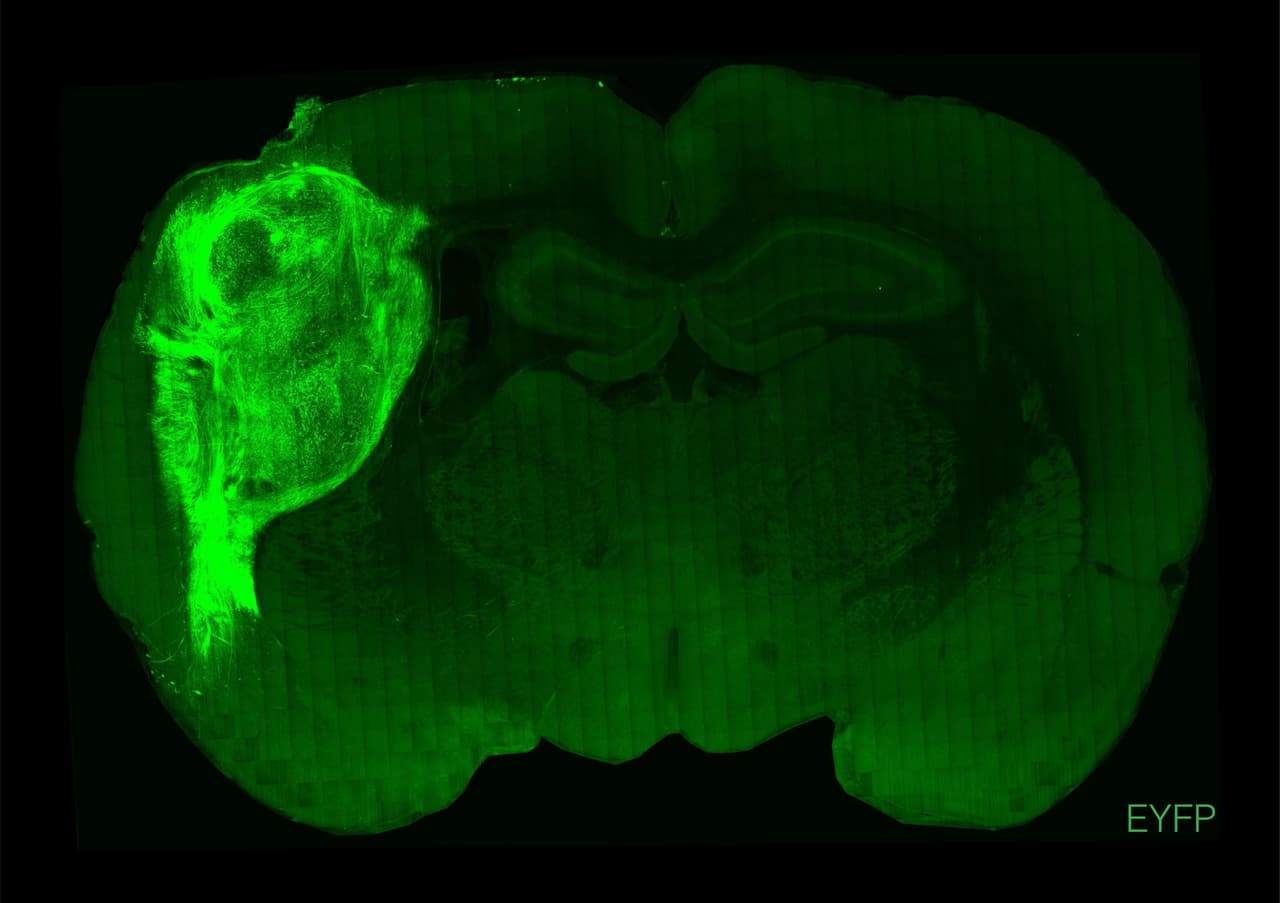

A los seis meses de implantados, llegaron a ocupar un tercio del hemisferio del cerebro de la rata en el que fueron injertados. Las neuronas se multiplicaron hasta alcanzar seis veces su cantidad inicial. Y algo todavía más sorprendente: formaron conexiones con los circuitos autóctonos de las ratas, como el tálamo, región encargada de transmitir las entradas sensoriales a la corteza cerebral.

Durante el experimento, luego de cultivados durante dos meses en el laboratorio, esos ‘organoides’ - ya muy similares a la corteza cerebral- fueron transferidos a los cerebros de ratas recién nacidas, fase en la que se forman las conexiones cerebrales.

Los científicos observaron cómo las células de las ratas pronto migraron y poblaron el tejido humano. Dentro de los roedores, los ‘mini cerebros’ humanos no sólo sobrevivieron, sino que se desarrollaron y crecieron.